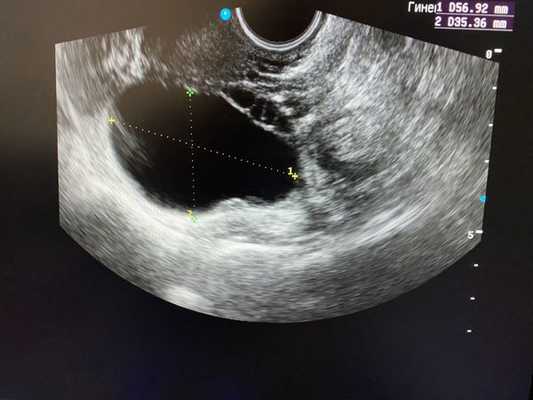

Как выглядят яичники при наличии кист:

При УЗИ-сканировании определяется шаровидное однокамерное образование от 3 до 8 см диаметром, заполненное однородным анэхогенным содержимым. Внутренние стенки кисты ровные, гладкие, имеют толщину 1—2 мм. На фоне фолликулярной кисты визуализируются участки интактной ткани яичника. При допплерометрии выявляются участки кровотока с невысокой скоростью, расположенные по периферии. Фолликулярную кисту дифференцируют от кистомы яичника. В неясных ситуациях прибегают к проведению диагностической лапароскопии.

Безусловно, проведение ультразвуковой диагностики трансабдоминальным и трансвагинальным датчиками позволит не только выявить локализацию кисты, но и определить ее структуру, размеры, характер жидкостного содержимого, определить тактику лечения пациентки. Особенностью фолликулярных кист при ультразвуковом исследовании является тонкостенная капсула с отсутствием сосочков внутренней стороны капсулы. [10] Диагностировать кистозные образования у беременных женщин значительно труднее, ввиду увеличения размеров матки на соответствующих сроках беременности, поэтому ультразвуковое исследование стоит проводить с ЦДК и доплерометрией [11] .

Учитывая тот факт, что наиболее часто встречаются фолликулярные ретенционные кисты (по данным гистологического исследования), наиболее актуальным является для сохранения фолликулярного резерва недопущение проведения резекции яичников. В настоящее время для лечения кист яичников широко применяется метод тонкоигольной аспирации с последующим цитологическим исследованием аспирата. Данный метод позволяет полностью сохранить существующий фолликулярный резерв, удалить кисту яичника, исследовать ее содержимое без операции, без наркоза, без потери трудоспособности.

Удаление кисты яичника методом тонкоигольной аспирации под контролем ультразвукового исследования проводится в условиях операционной.

Под местной аппликационной анестезией 10% раствором Лидокаина (спрей 6 доз), используется аппарат для УЗИ с влагалищным датчиком и стерильным пункционным адаптером. Ультразвуковым датчиком в боковой свод влагалища выводится яичник с кистой на пункционную линию, и через влагалище иголкой 16G проводится пункция кисты.

После введения иглы в полость кисты яичника шприцом проводится аспирация ее содержимого. Проводится визуальный осмотр полученного аспирата, измеряется количество и оценивается его характер (цвет, наличие примесей). Аспират обязательно должен направляться на цитологическое исследование в онкологический диспансер.